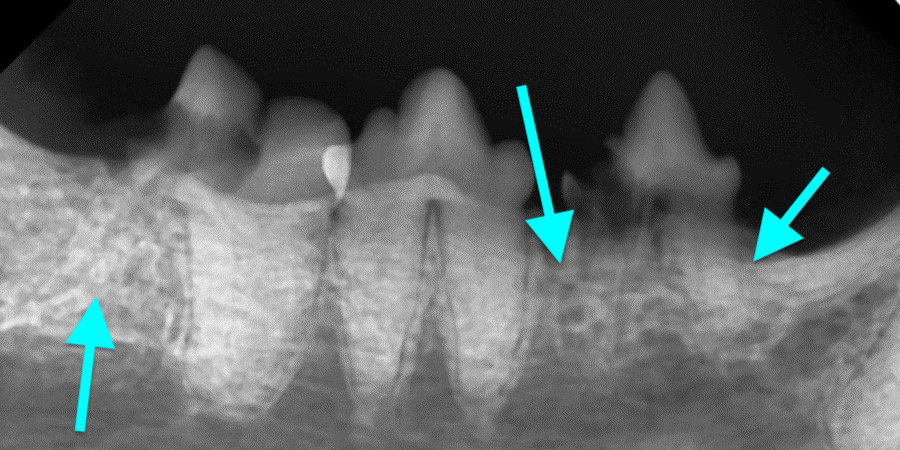

Внутриротовые рентгенограммы всей полости рта являются важным диагностическим инструментом, помогающим выявлять и классифицировать резорбцию зубов. Нередко резорбция, отмеченная на одном зубе, выявляется на таком же зубе симметрично.Существуют два широко используемых метода классификации резорбции зубов у кошек на основании радиографической картины (по стадии и типам). Рентгенологическая картина резорбции зуба варьируется от незначительных рентгенопрозрачных дефектов поверхности зуба в области цементно-эмалевой границы до обширной резорбции замещающего корня, придающей зубу пятнистый или изъеденный молью вид. Планирование лечения также включает рентгенографическую оценку пространства периодонтальной связки.

Классификация по типам рентгенологических проявлений резорбции зубов1 (фото 17):

Тип 1: наблюдается потеря альвеолярной кости, примыкающей к области резорбции зуба, на других участках зуба сохраняется нормальное пространство периодонтальной связки.

Тип 2: потеря пространства периодонтальной связки и цемента зуба из-за сращения корня зуба с альвеолярной костью (дентоальвеолярный анкилоз), резорбирующаяся структура зуба выглядит менее рентгеноконтрастно, чем неповрежденный зуб.

Тип 3: комбинация типов 1 и 2.